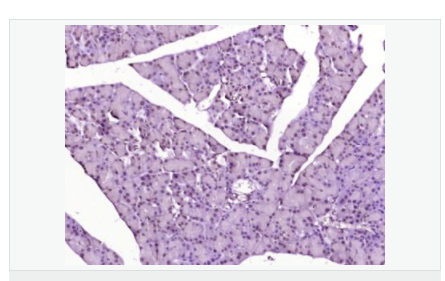

| 產(chǎn)品應(yīng)用 | WB=1:500-2000 ELISA=1:5000-10000 IHC-P=1:100-500 IHC-F=1:100-500 IF=1:100-500 (石蠟切片需做抗原修復(fù)) not yet tested in other applications. optimal dilutions/concentrations should be determined by the end user. |

| 產(chǎn)品介紹 | Acts as a growth inhibitor. Can activate TP53/p53, causes G1 arrest and collaborates with CDKN2A to restrict proliferation, but does not require either protein to inhibit DNA synthesis. Redistributes CDKN2A into the nucleoplasm. Involved in maintaining chromosomal stability. There are two isoforms. Function: Acts as a growth inhibitor. Can activate p53/TP53, causes G1 arrest and collaborates with CDKN2A to restrict proliferation, but does not require either protein to inhibit DNA synthesis. Redistributes CDKN2A into the nucleoplasm. Involved in maintaining chromosomal stability. Subunit: Interacts with CDKN2A and MDM2. Subcellular Location: Nucleus. Tissue Specificity: Widely expressed at low levels in most tissues, with highest levels in pancreas, lung and liver. Expression is decreased in primary tumors including lung, liver, breast, pancreas and kidney carcinomas, chronic lymphocytic leukemia and diffuse large B-cell lymphoma. Post-translational modifications: Ubiquitinated; mediated by MDM2 and leading to its subsequent proteasomal degradation. Similarity: Belongs to the TBRG1 family. Contains 1 FYR C-terminal domain. Contains 1 FYR N-terminal domain. SWISS: Q3YBR2 Gene ID: 84897 Database links: Entrez Gene: 84897 Human Entrez Gene: 21376 Mouse Omim: 610614 Human SwissProt: Q3YBR2 Human SwissProt: Q3UB74 Mouse Unigene: 436410 Human Unigene: 28689 Mouse Unigene: 129282 Rat Important Note: This product as supplied is intended for research use only, not for use in human, therapeutic or diagnostic applications. |